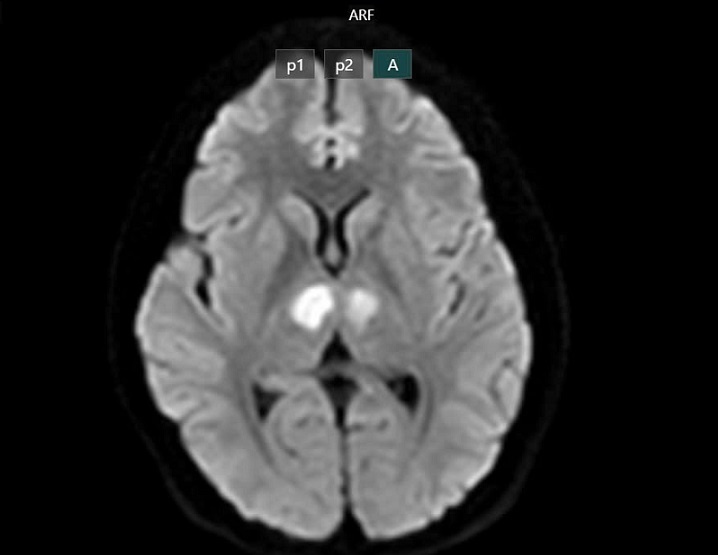

Phim chụp cho thấy não bệnh nhân bị tổn thương vùng đồi thị hai bên vì dùng thuốc giảm cân chứa chất cấm. Ảnh: BVCC.